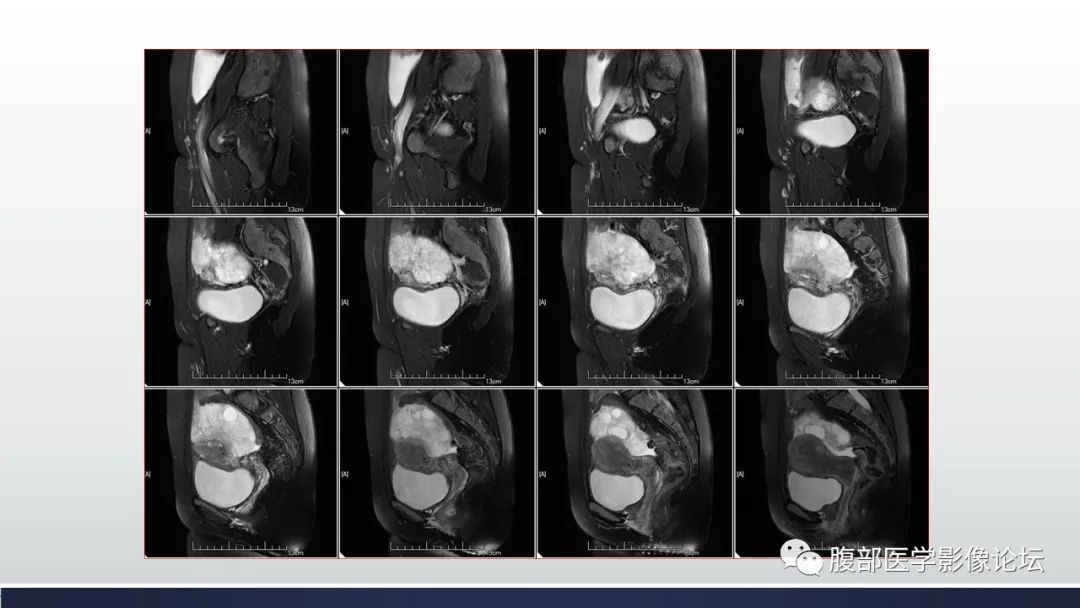

【病例】子宫内膜透明细胞癌1例MR-7

【病例】子宫内膜透明细胞癌1例MR-8